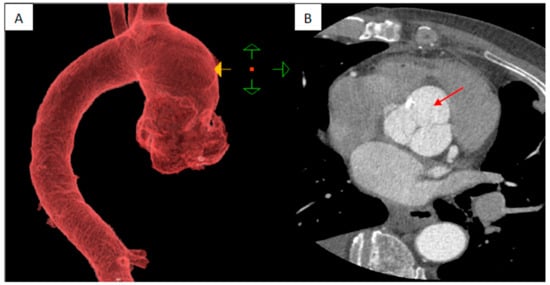

2. Case Report

Surgical Technique